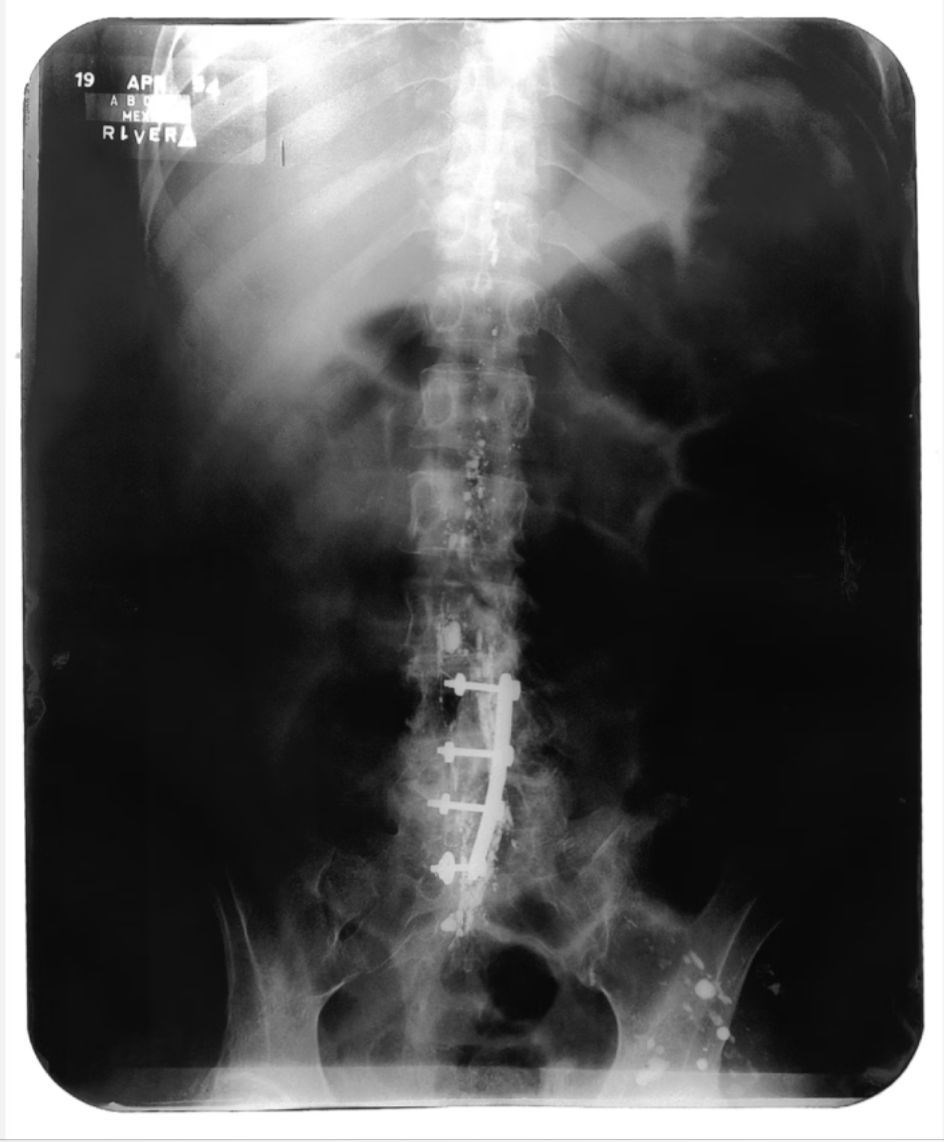

کالو در سال ۱۹۰۷ در مکزیک متولد شد. در ۶ سالگی به فلج مبتلا شد و در ۱۸ سالگی به‌دلیل تصادف شدید دچار رنج و دردی مزمن شد که تا پایان عمر همراه او بود؛ اثراتی که در مضامین آثارش به‌سادگی قابل لمس است. او در سال ۱۹۲۹ با دیگو ریورا (Diego Rivera)، نقاش دیواری مشهور مکزیکی، ازدواج کرد؛ پیوندی پرتلاطم که بر درد و رنج زندگی کالو افزود. با‌این‌حال این ازدواج در زندگی حرفه‌ای او تأثیر چشمگیری داشت. لباس‌های مکزیکی، زیورآلات خاص و ابروان پیوسته به امضایی مشخص برای کالو تبدیل شد. کالو یکی از تأثیرگذارترین زنان هنرمند قرن بیستم است. او در ۱۹۵۴ از دنیا رفت.